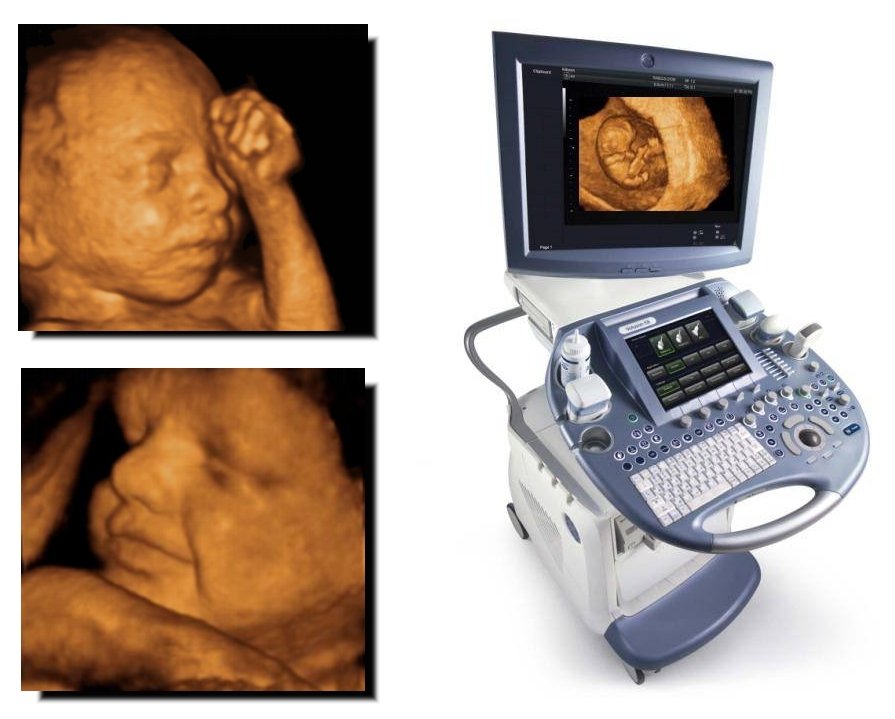

Трёхмерное УЗИ, как и все остальные методы ультразвуковой диагностики, проводят при помощи датчика, который генерирует ультразвуковые волны и принимает отражённые эхосигналы, видоизменённые в электрические импульсы. В итоге все данные, полученные в виде картинки, отображаются на мониторе. Однако при 3Д УЗИ используют более крупный датчик, в корпус которого встроен двумерный датчик, находящийся в постоянном движении. Ультразвуковые волны при трёхмерном УЗИ направляются не сверху вниз, как при обычном УЗИ, а под различными углами. Это позволяет будущим родителям увидеть все части тела ребёночка, а также получить его объёмное изображение.

Первый «трёхмерный» аппарат появился в 1989 году в Австрии. Тогда качество изображения было очень низким, да и ждать его нужно было больше получаса. Поэтому метод особого энтузиазма не вызвал. Первый сканер, с возможностью трехмерной реконструкции в реальном времени, появился только в 1996 году.